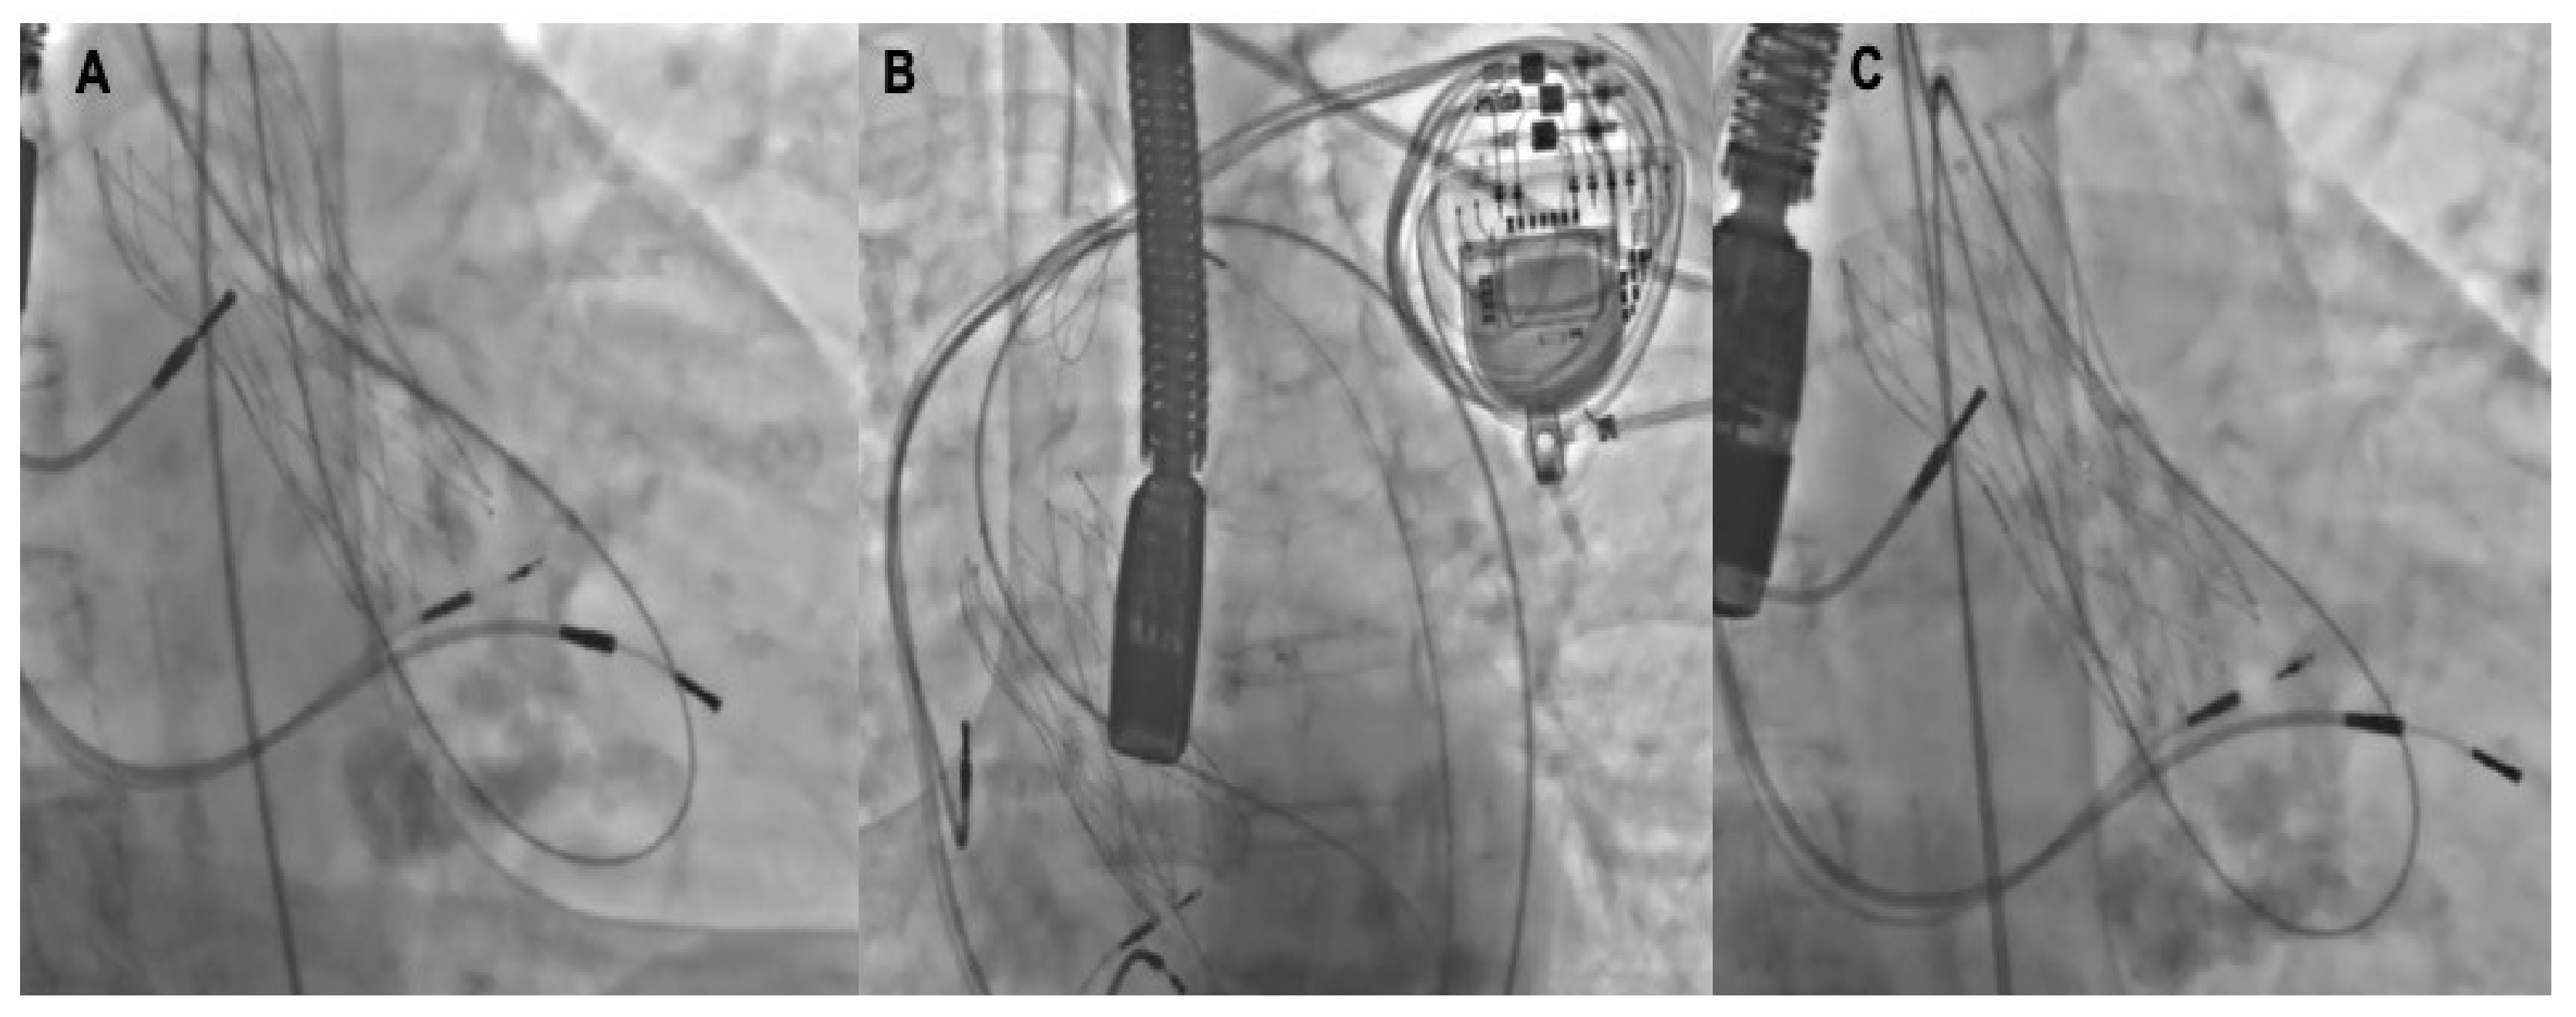

Figure 3.

Tips and tricks for support improvement. A 5-Fr Amplatz left catheter (AL-1) (A) is across the leak and the 0.035–260 cm hydrophilic guidewire placed in the left ventricle is advanced back through the center of the valve and then snared in the ascending aorta (B) and externalized through another arterial access, creating a supportive arterio-aorta rail (C) to retrogradely advance the delivery sheath.